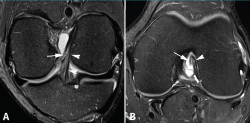

Figura 5. Rotura parcial del fascículo posterolateral (PL) del ligamento cruzado anterior (LCA). Corte oblicuo coronal (A) y axial (B) de resonancia magnética (RM) potenciados en densidad protónica con supresión grasa que muestran una rotura completa proximal del fascículo PL (flechas). Fascículo anteromedial normal (cabezas de flecha).